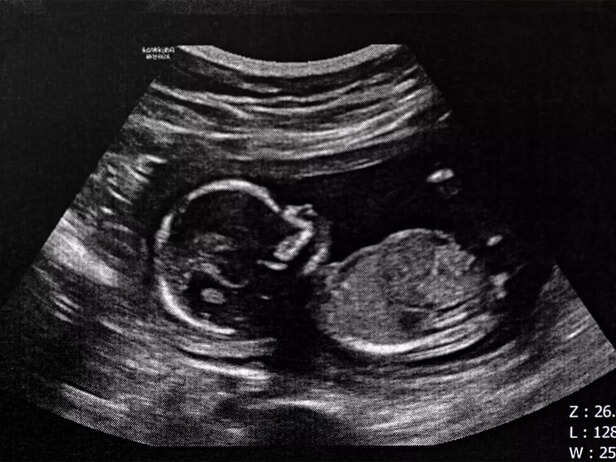

baby fetus

While your baby's bones are solidifying, one exception is the skull. To ease a smoother journey through the birth canal, your baby's skull bones remain somewhat pliable. This allows for compression during delivery.